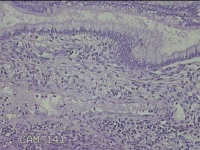

宫颈赘生物

性别

女

年龄

32岁

临床诊断

宫颈息肉;贫血

一般病史

发现宫颈赘生物半天。

标本名称

大体所见

灰白粉红色肿物0.7x0.3x0.2cm一个,表面光滑。